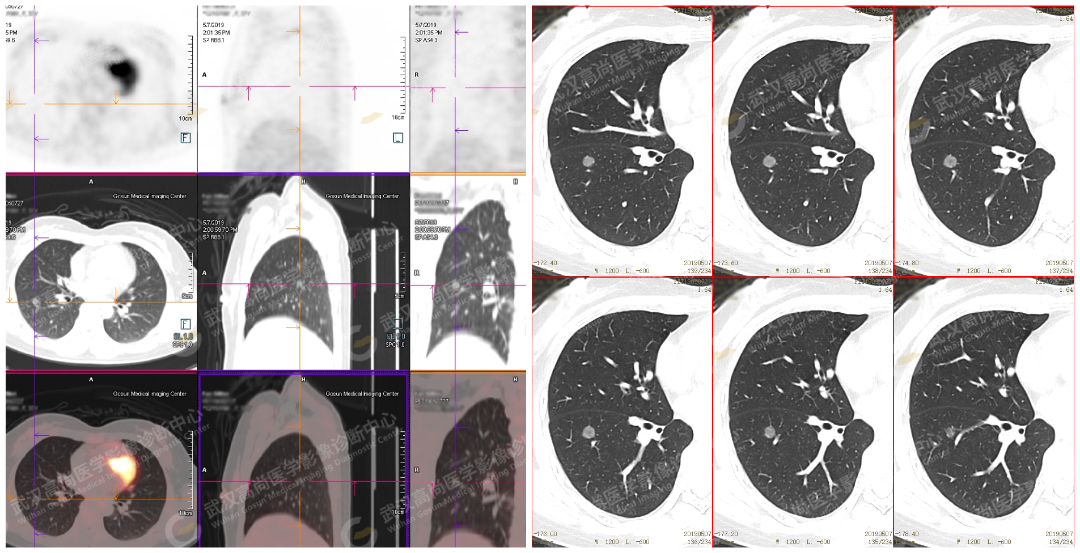

右下肺磨玻璃结节,密度外高内低「反晕」征,界清,无毛刺、分叶等征象,代谢未见增高(隐源性机化性肺炎)

左上肺大片状磨玻璃影,密度外高内低,边缘代谢明显增高,SUVmax 为 5.1,SUVmin 为 4.2(感染性病变:真菌/TB)

右肺下叶混合磨玻璃结节,中央实性结节占比 50% 左右,代谢轻度增高,SUVmax 为 2.7,SUVmin 为 2.5

磨玻璃边缘模糊,无支气管截断及血管纠集征,多考虑为肉芽肿性炎